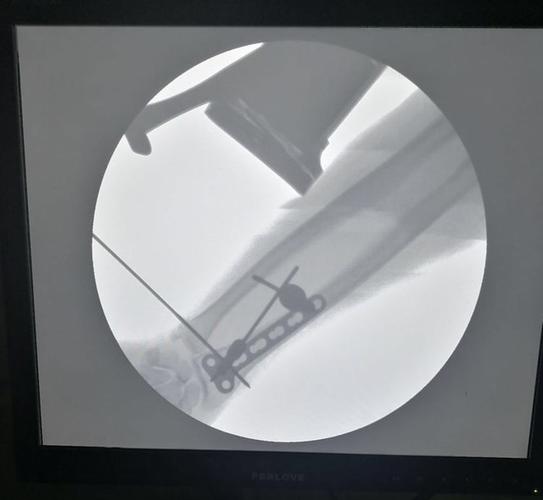

骨折接骨,跖骨骨折

手术演示:盖氏骨折微创钢板接骨术

接骨手术